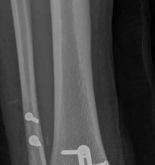

Definitive Lag Screw and Plate Fixation

The definitive fixation sequence is critical to achieving absolute stability:

1. Independent Lag Screws: If the fracture morphology permits, independent lag screws are placed perpendicular to the fracture plane. The standard sequence is utilized: 4.5mm gliding hole in the near cortex, insertion of the drill sleeve, 3.2mm thread hole in the far cortex, countersinking, measuring, tapping, and screw insertion.

2. Plate Application: A pre-contoured anatomic locking plate or a standard buttress plate (e.g., L-buttress or T-plate) is applied to the lateral cortex. The plate must sit flush against the bone at the apex of the fracture.

3. Diaphyseal Fixation First: To achieve the buttress effect, the plate is first secured to the intact distal diaphyseal segment using cortical screws. If the plate is slightly under-contoured, tightening these diaphyseal screws will drive the proximal portion of the plate into the metaphyseal flare, compressing the articular fragment.

4. Periarticular Screws: Subchondral "rafting" screws are then inserted through the proximal holes of the plate. These screws support the elevated articular cartilage and neutralize any remaining forces. In modern osteosynthesis, locking screws are frequently utilized in the periarticular segment to create a fixed-angle construct, which is particularly beneficial in osteopenic bone.

Image